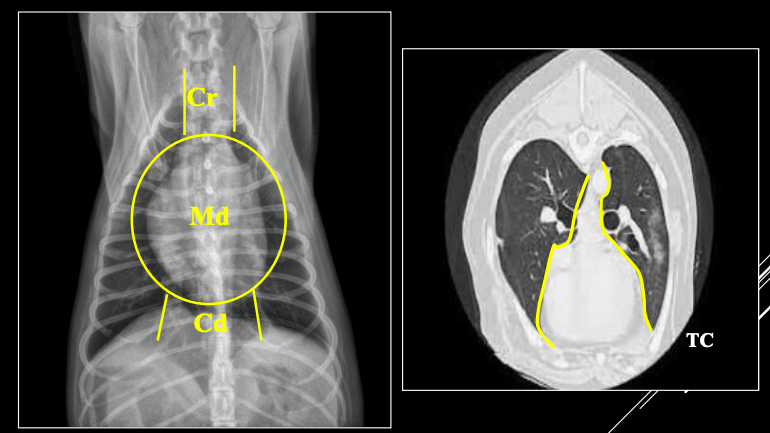

PARTES DEL MEDIASTINO

- Craneal (Cr): Nervios, nodulos linfaticos, vasos (Arteria subclavia izquierda, tronco braquicefalico, vena cava craneal, vena acigos...)

- Medio (Md)

- Caudal (Cd)

Órganos mediastínicos visibles:

- Esófago (a veces), timo (jóvenes), tráquea, corazón, aorta, VCC.

Órganos no visibles:

- Vasos (A. subclavia izda., tronco braquiocefálico, V. cava craneal, V. ácigos).

- Nervios.

- Nódulos linfáticos.